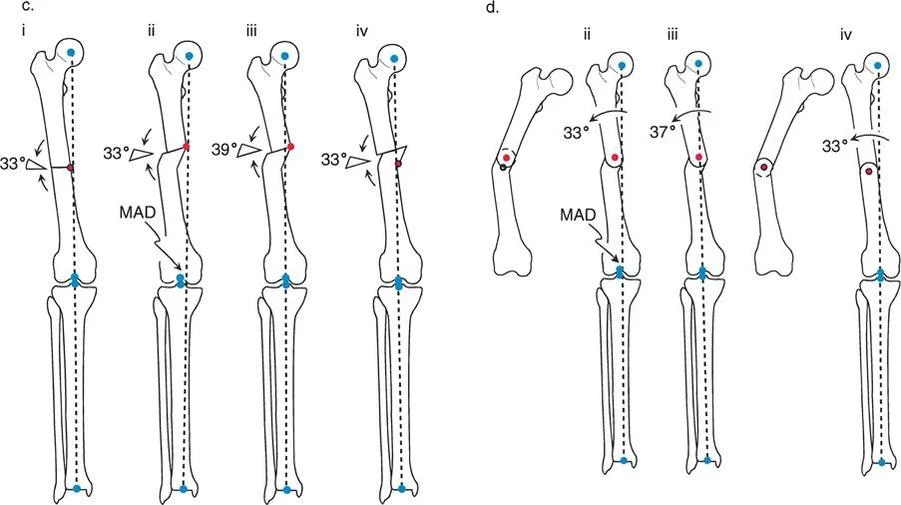

Paley Three Rules of Osteotomy

The cornerstone of frontal plane realignment lies in Paley's three osteotomy rules. Understanding these rules allows the surgeon to predict exactly how the mechanical axis, anatomic axis, and bone ends will shift upon correction. Mastery of these rules is what separates a master deformity surgeon from a novice.

Osteotomy Rule One Pure Angulation

The Geometric Definition

When the osteotomy line and the ACA both pass directly through the CORA, pure angular correction is achieved.

The Biomechanical Result

The mechanical axis is fully restored to normal. Because the bone is cut exactly at the apex of the deformity and hinged at that exact same apex, there is no translation of the bone segments. The anatomic axis realigns perfectly without any "step-off" or cortical bump. The proximal and distal bone segments will have maximum bony contact, promoting rapid union.

Clinical Application

This is the ideal surgical scenario. It is most easily achieved in diaphyseal deformities where the CORA lies in the midshaft, allowing the surgeon to safely cut exactly at the apex of the deformity. It is highly amenable to intramedullary nailing, as the re-established collinear anatomic axis allows for smooth passage of the guidewire and nail.

Osteotomy Rule Two Angulation with Translation

The Geometric Definition

When the ACA passes through the CORA, but the osteotomy line is made at a different level (either proximal or distal to the CORA).

The Biomechanical Result

The mechanical axis and joint orientation angles are perfectly restored. However, because the bone cut is made at a distance from the hinge point, the bone segments will mathematically translate relative to one another. This creates a visible "bump" or step-off in the anatomic axis. While the bone looks jagged on an x-ray, the load-bearing mechanical axis is flawless.

Clinical Application

Rule Two is frequently used for juxta-articular deformities. For example, if a patient has a severe distal femoral valgus deformity, the CORA may be located inside the knee joint. A surgeon cannot perform an osteotomy through the articular cartilage. Therefore, the surgeon must place the ACA at the joint (the true CORA) but perform the actual bone cut (osteotomy) safely in the metaphysis.

The resulting translation is not an error; it is a necessary and mathematically sound compromise to achieve a straight mechanical axis while cutting the bone in a biologically safe zone.

Osteotomy Rule Three Secondary Deformity

The Geometric Definition

When the osteotomy line and the ACA are both placed at a level different from the CORA.

The Biomechanical Result

A secondary translational deformity is created. While the angular deformity may appear to be corrected, the mechanical axis will not be fully restored. The proximal and distal mechanical axes will be parallel but not collinear, resulting in residual Mechanical Axis Deviation (MAD).

Clinical Application

In most cases, Rule Three represents an unintended surgical error. If a surgeon ignores the CORA and simply cuts the bone where it is most convenient, hiving it at the cut site, they will create a "golf club" deformity. The joint may be parallel to the floor, but the mechanical axis will be shifted, leading to rapid joint degeneration.

However, Rule Three can be used intentionally by master surgeons to correct pre-existing translational deformities. If a bone has a pre-existing translation, applying Rule Three can create an equal and opposite translation, effectively realigning the mechanical axis.